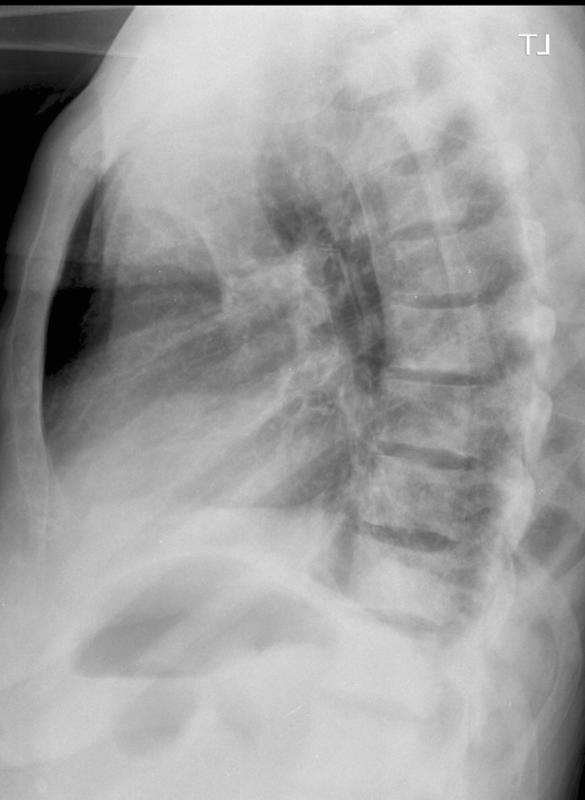

Breast mets